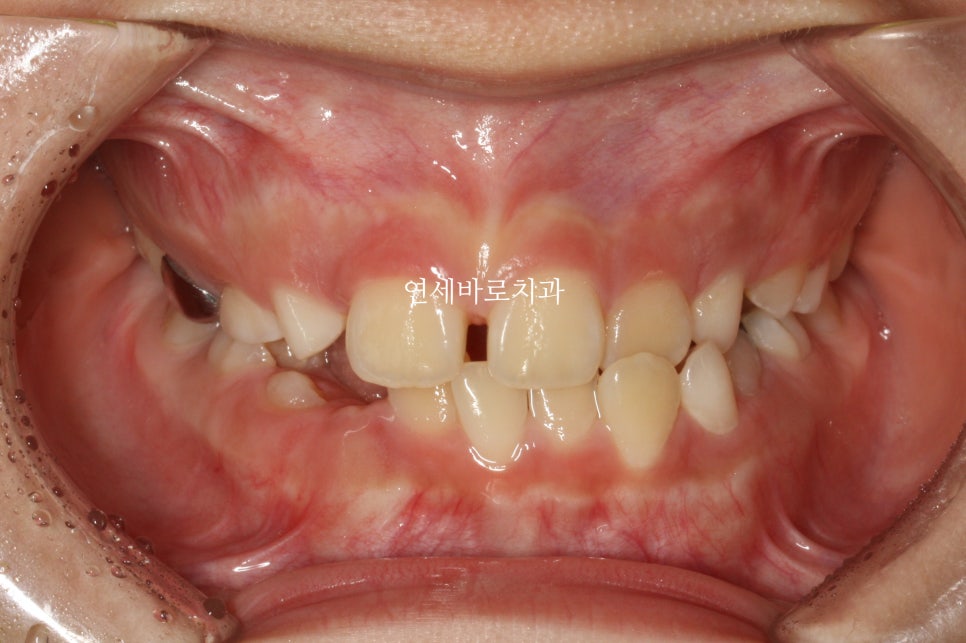

처음에 왔을때 모습입니다.

아이는 선천적으로 앞니 하나가 없는 상태였습니다.

골격적으로 비대칭도 있었지만, 중안모함몰과 약간의 주걱턱경향이 관찰되었습니다.